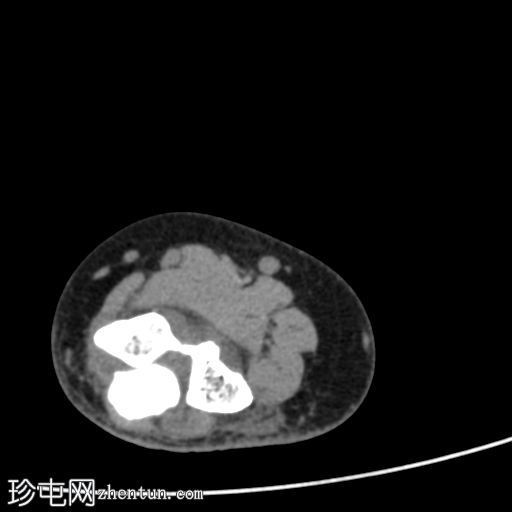

轴向软组织窗

显示整个桡骨头粉碎性骨折,特征为两个以上大骨折块,以及倾斜且受压的关节节。

这表明该骨折为不稳定骨折,根据Mason桡骨头骨折分型,为IIIC型。

远端肱骨和可见尺骨未见骨折征象。

此外,由于关节积血导致关节扩张,肘关节脂肪平面弯曲。